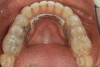

(13.) Postoperative occlusal view of upper arch.

Figure 13

(14.) Postoperative occlusal view of lower arch.

Figure 14

After the composite veneers were finalized, impressions were taken for a monolithic lithium disilicate crown on tooth No. 12. This was placed during a subsequent appointment, and occlusal equilibration was carried out. The patient returned for final photographs a couple of weeks later (Figure 10 through Figure 14).